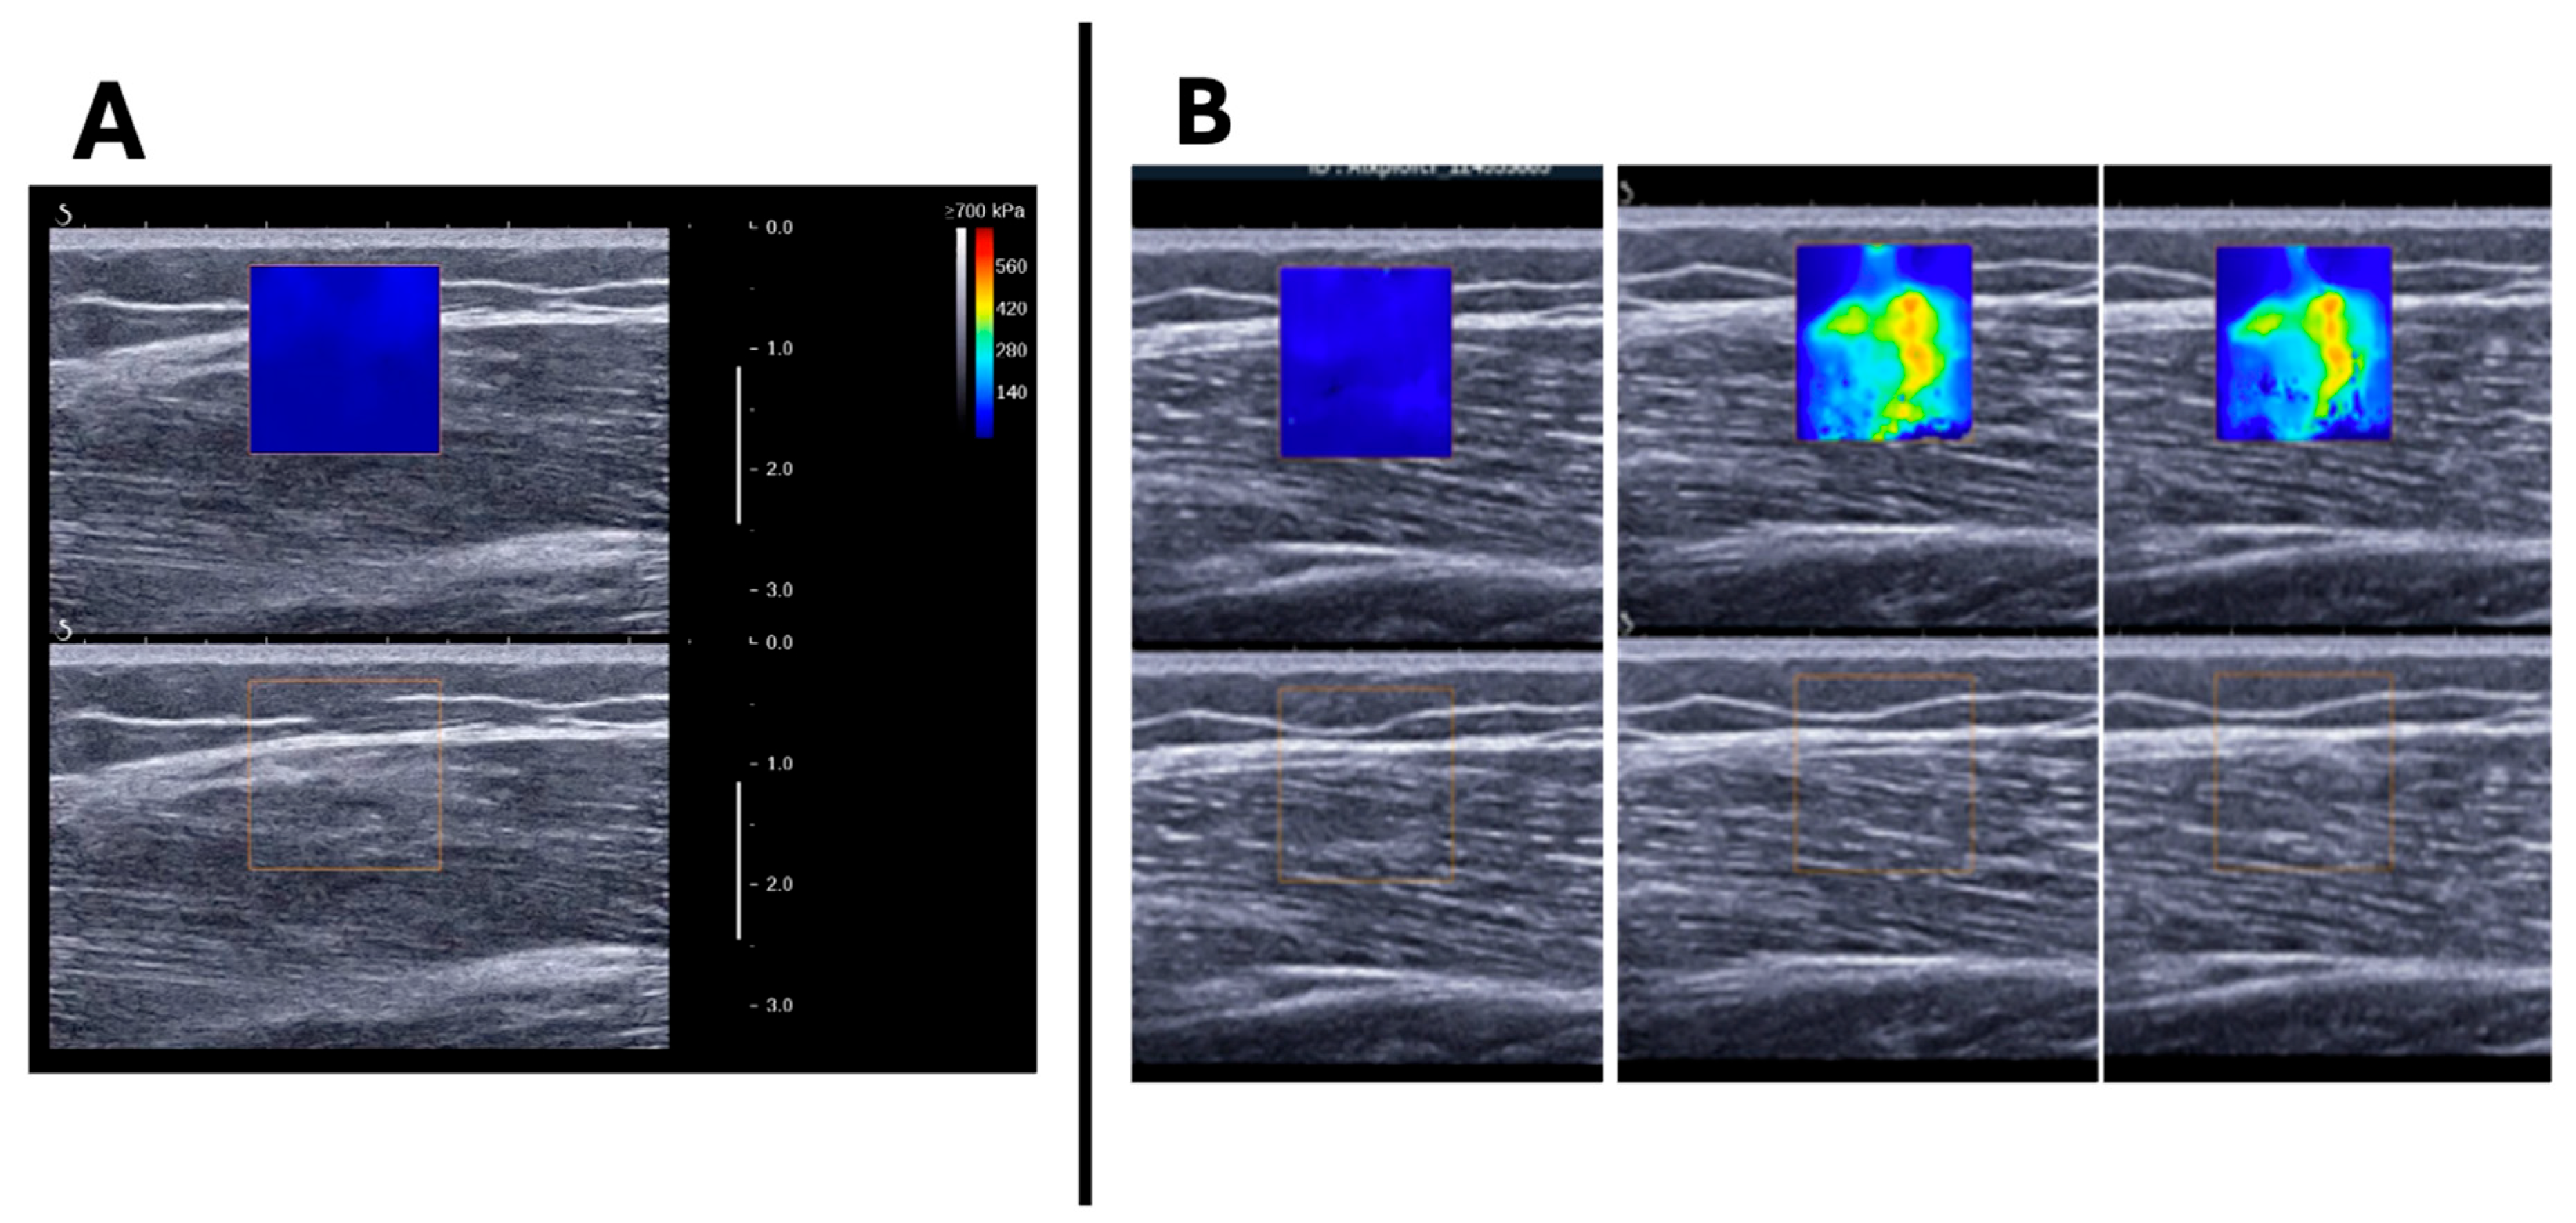

The SSI field of view was defined by a fixed-size square region of interest (ROI) measuring 1.5 × 1.5 cm, positioned within the VL, away from fibrous and adipose septa, and between the superficial and deep fascia (Figure 3).

Figure 3.

Example of image acquisition in longitudinal view: (A) image of vastus lateralis muscle and subcutaneous adipose tissue with and without the SII ROI (the ROI was reduced to 1.5 cm2 to avoid the superficial fascia and adipose tissue). (B) MP4 video acquired was converted into JPEG images and changes in color within the ROI were analyzed.